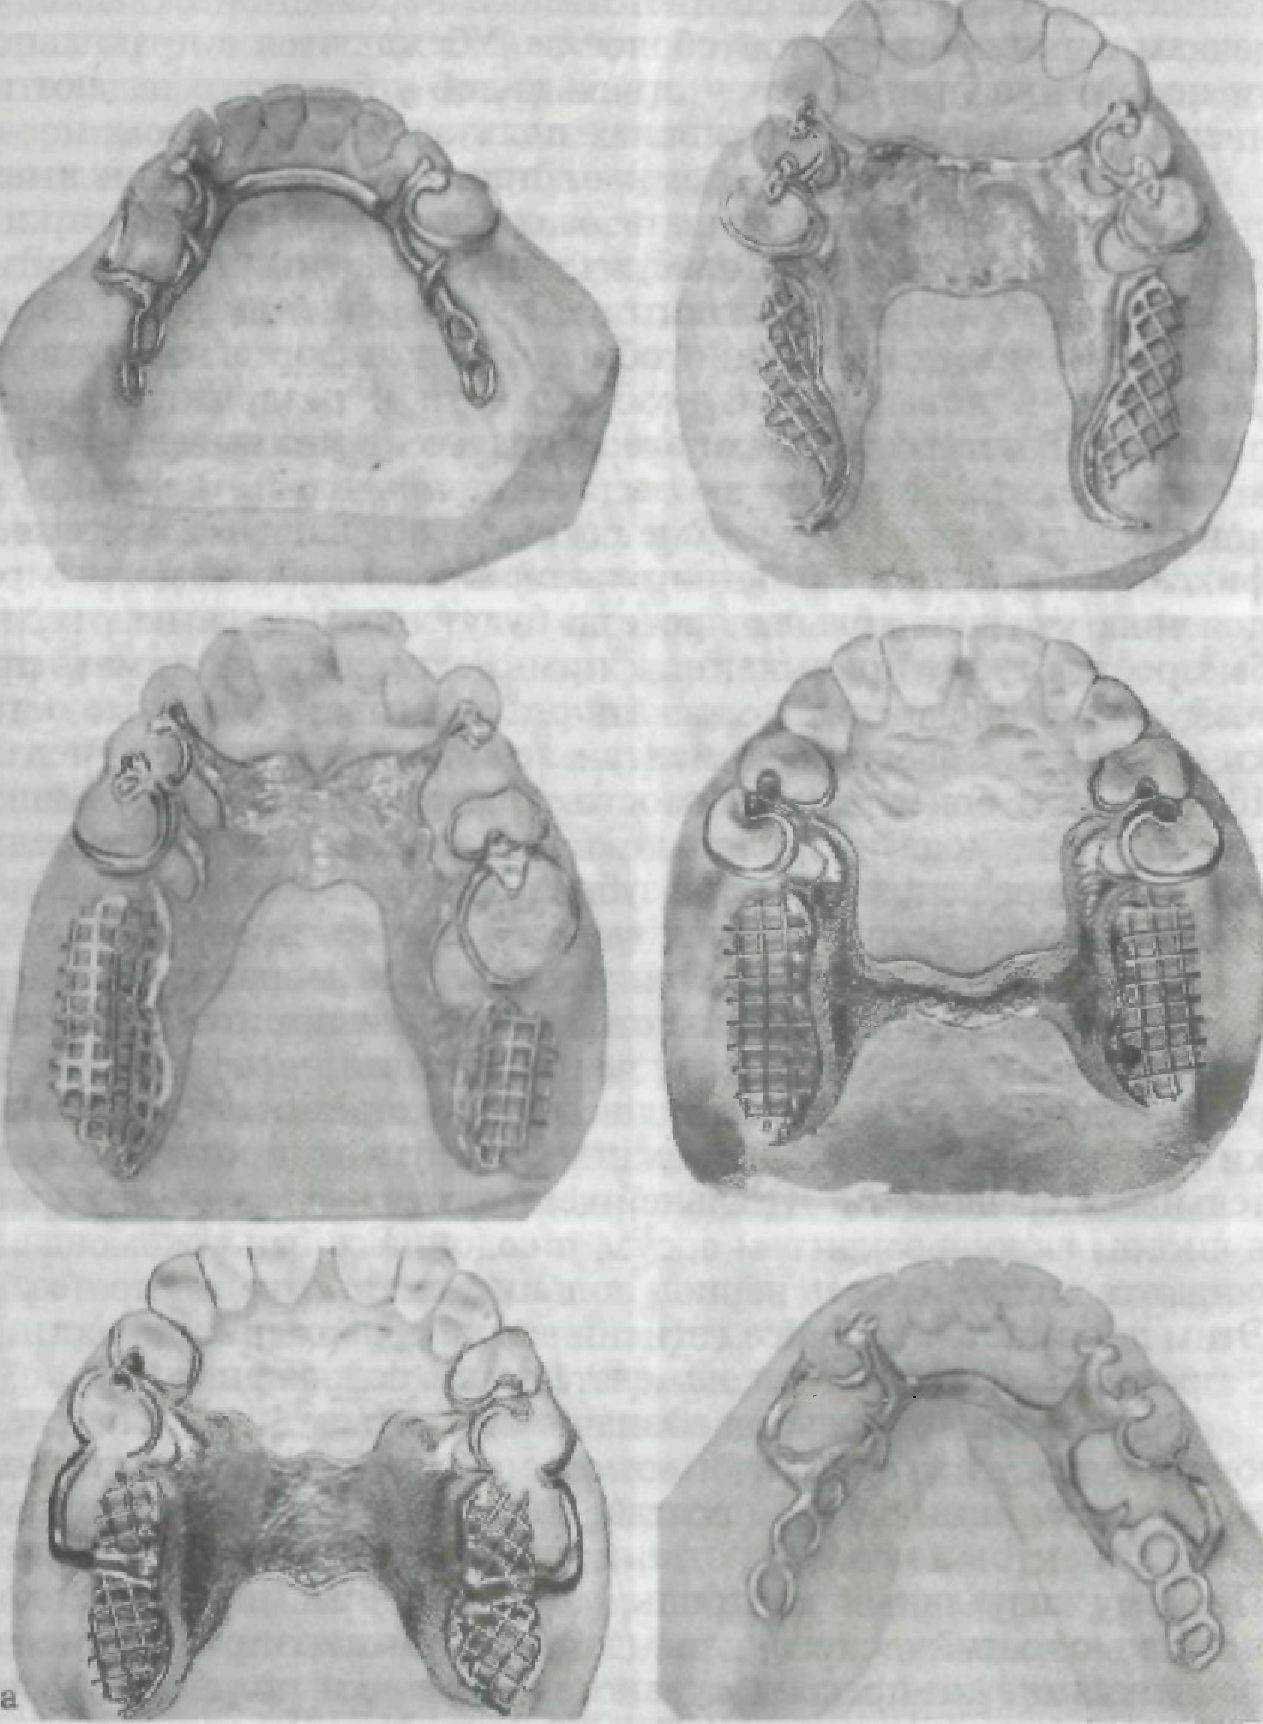

На рис. 131—133 представлены варианты дефектов зубных рядов, варианты врачебных решений по выбору конструкций съемных протезов. Схемы на рисунках позволят студенту самостоятельно осмыслить обоснование выбора конструкции съемного протеза.

Рис. 131, а

Рис. 131. Протезы, применяемые при лечении адентий. а — варианты I класса по Кенеди; б — варианты II класса по Кенеди.